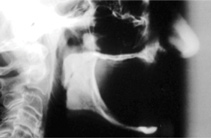

The Toronto Conference in 1982, chaired by Professor George Zarb and presented by Professor Per-Ingvar Brånemark, was a seminal event that changed edentulous treatment planning concepts irrevocably. No longer was it necessary to rebuild lost bone through grafting alone in either arch. The severely atrophic mandible, for example, could be treated with as few as four implants used to support a bone-sparing prosthesis through integrated tooth analogs, as demonstrated in Figure 1 through Figure 3. Here, an 81-year-old patient presented with severe mandibular atrophy (Figure 1) from denture wear since a very young age and had a history of being unable to manage a mandibular prosthesis despite numerous attempts at new denture construction. Four vertical machined-surface osseointegrated implants were placed in 1983 by Professor Brånemark, and all four penetrated the inferior cortex up to 3 mm to 4 mm in depth, as shown on the immediate postoperative panoramic film (Figure 2). At 4 years and 5 months, reparative bone had formed to the apices of all implants (Figure 3), and all of them remained in uncompromised function until the patient passed away at age 90.

Fig 2. Four vertical machined-surface osseointegrated implants placed in 1983 penetrated the inferior cortex up to 3 mm to 4 mm in depth, immediate postoperative.

Figure 2

Fig 3. At 4 years and 5 months follow-up, reparative bone had formed to the apices of all implants.

Figure 3